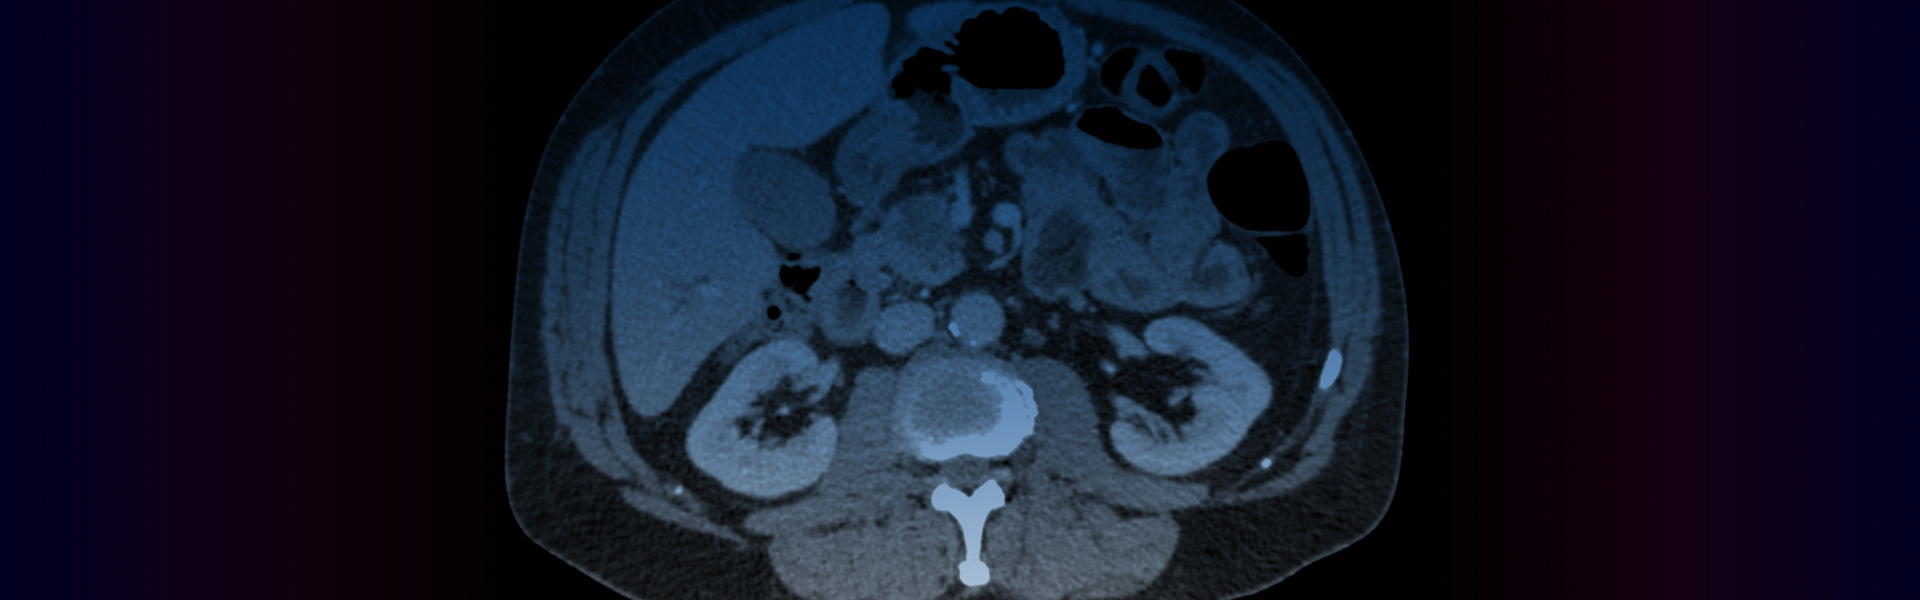

- Pancreatic Cancer Programme

The Pancreatic Cancer Programme, formerly known as Cambridge Pancreatic Cancer Centre (CPCC), is now one of the ten foundamental programmes within Cancer Research UK (CRUK) Cambridge Centre. We believe that clusters of multi-disciplinary excellence is the key to overcome the challenges in treating pancreatic cancer. Focusing on world-class trials of therapies showing effectiveness in research models, we aim to help patients seeking cutting-edge treatment opportunities.